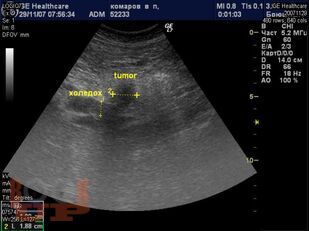

Диагностика и лечение механической желтухи

Учебно-методическое пособие посвящено актуальным проблемам этиологии, патогенеза, диагностики, современным методам консервативного и оперативного лечения механической желтухи. Представлены новые классификации, схемы консервативного лечения, современные виды оперативного лечения, учитывая утвержденные клинические рекомендации Российского общества хирургов (2018 г.). Издание иллюстрировано рисунками, таблицами, имеются тестовые задания и задачи. Пособие предназначено для слушателей дополнительного профессионального образования и ординаторов, обучающихся по специальности 31.08.67 Хирургия.